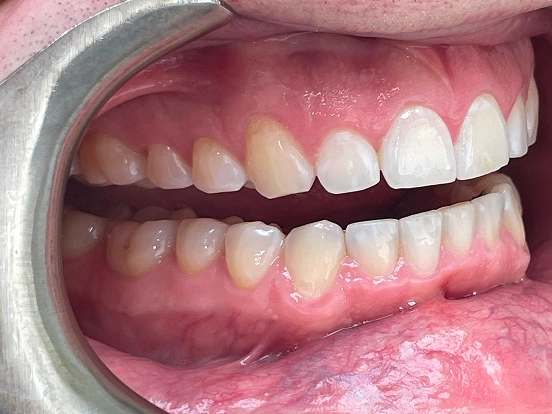

Invisalign DT

DT’s transformation with Invisalign is a perfect example of how advanced orthodontic technology can deliver incredible results. The clear aligners gradually corrected the alignment and bite issues, creating a straighter, healthier, and more attractive smile—all without noticeable brackets or wires.